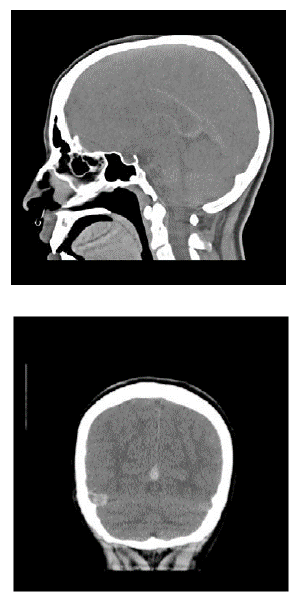

Al ingreso manifestaba intenso dolor cervical, afasia motora, desviación de la mirada a la derecha, sialorrea, hemiparesia izquierda, Babinsky izquierdo, reflejo rotuliano izquierdo exaltado y no mostraba alteración en la sensibilidad ni signos meníngeos. Su talla es de 173 cm (por encima del percentil 95), delgada, extremidades largas y con aracnodactilia. El TAC cerebral simple evidenció trombosis de varios senos venosos (figura 1); el estudio se complementó con Angio TAC cerebral (figura 2), resonancia magnética cerebral (figura 3) y Angio resonancia cerebral contrastada (figura 4), que confirman la trombosis de los senos venosos. Después de diagnosticar accidente isquémico se trasladó a la unidad de cuidados intensivo (UCI) y se anticoagula con enoxaparina. No necesitó soporte inotrópico ni ventilatorio y posteriormente se llevó a pisos. El ecocardiograma y el doppler carotideo fueron normales. No se encontró dislipidemia y el estudio de enfermedad autoinmune fue negativo. Los exámenes para trombofilia, tomados en etapa aguda, solo mostraron una proteína S ligeramente disminuida (57 %, VN de 59 a 118 %), al igual que la antitrombina m (58,8 %, VN 83-128 %). Se ampliaron estudios con ácido fólico y vitamina B12 en sangre, al igual que los ácidos orgánicos en orina por cromatografía; todos estaban normales. Los aminoácidos en sangre mostraron elevación de la metionina (63 µmol/L, VN de 10 a 45 µmol/L) y la homocisteina (3 µmol/L, VN de 0 a 1 µmol/L) con cistationina baja (0, VN de 0 a 3 µmol/L). El estudio de homocisteina en sangre fue de 214 µmol/L (VN en mujer de 5,08 A 15,39 µmol/L), lo que confirmó el diagnóstico de homocistinuria por deficiencia de CBS.